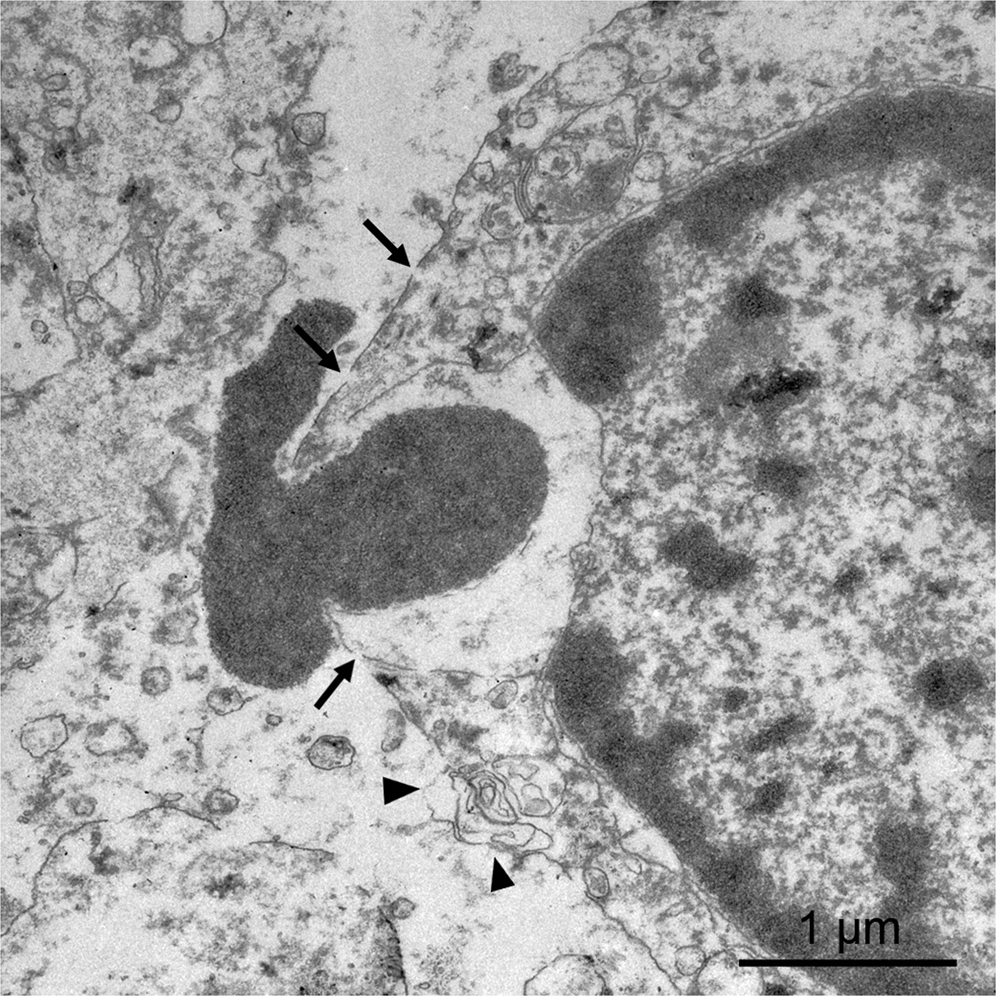

Figure 10

TEM 3 days after IRE. The plasma membrane of the hepatocytes shows small pores (arrows) together with large areas in which the membrane has disappeared (arrowheads). Amounts of chromatin are expelled from the nucleus to extracellular space.